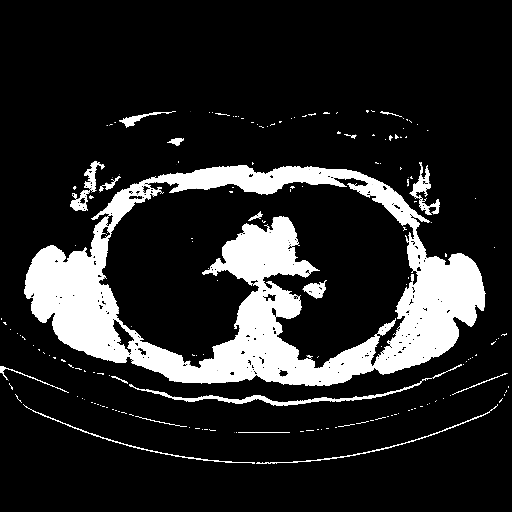

Image Grid

4Γ—3 grid: Rows show different image types (Original NATIVE, Reconstructed NATIVE, Original VENOUS, Generated VENOUS), Columns show windowing techniques (No Window, Lung Window, Mediastinum Window)

Original NATIVE CT scan (input)

Full window (WL 1023.5, WW 4095 β†’ Low βˆ’1024, High +3071)

Actual HU range: [-1024.0, 3071.0]

Reconstructed NATIVE CT scan (cycle consistency)

Original VENOUS CT scan

Generated VENOUS CT scan (A→B translation)